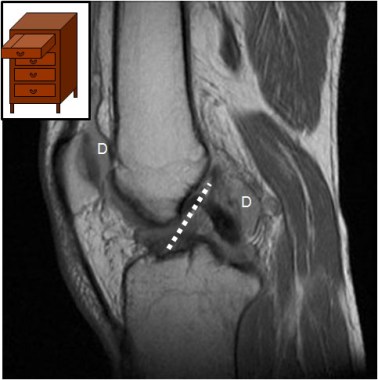

SIGNO DEL CAJÓN ANTERIOR

Signo de rotura del ligamento cruzado anterior en Resonancia magnética. Consiste en el desplazamiento anterior (subluxación) de la tibia con respecto al fémur, equivalente al signo clínico del cajón anterior. La línea blanca de puntos indica la localización teórica del ligamento cruzado anterior. Se observa derrame en varios compartimentos articulares (D).